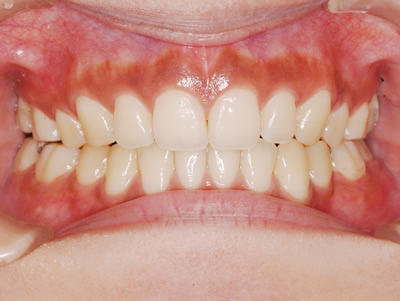

永久歯に交換するためのスペース不足による前歯のガタガタで、取り外しができる拡大床にて上下顎の幅を拡大した後、上顎の前歯をマルチブラケット装置で並べました。治療の期間は1年9か月でした。

初診時

終了時

| 費用の目安 | 440,000(税込) | |

| 治療期間の目安 | 1年9が月 | |